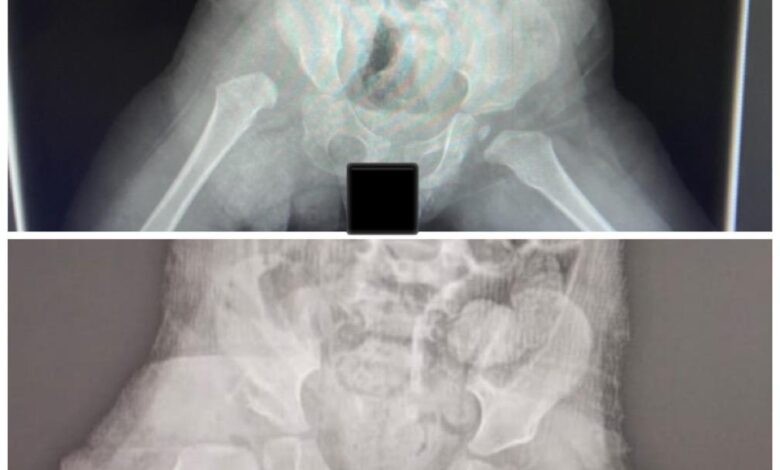

تمكّن – بفضل الله فريق طبي متخصص بجراحة عظام الأطفال بمستشفى الدرعية عضو تجمع الرياض الصحي الثالث ، في إعادة خلع الورك الولادي لطفلة بعمر 17 شهر .

وأوضح تجمع الرياض الصحي الثالث أن الطفلة كانت تعاني بسبب عرجة شديدة نتيجة خلع مفصل الورك، والذي بدوره سبب لها معاناة في المشي وسيتسبب مستقبلاً في حال عدم علاجه في آلام مزمنة وخشونة مبكرة، واصفًا تلك الحالة بأنها معقدة لكون أنه لم تُجر لها عملية إعادة الخلع بوقتٍ مبكر.

وأضاف أنه تم من خلال فريق طبي يُشرف عليه استشاريي جراحة عظام الاطفال ، إجراء الفحوص والأشعات اللازمة وتهيئة متطلبات عملية التدخل الجراحي لإعادة خلع الورك لدى الطفلة، وتم بالشكل المطلوب، حيث استمرت العملية ساعتين تم خلالها إرجاع مفتوح لمفصل الورك. مع قص عظمة الحوض لتحسين التغطية وتثبيتهما مع تحرير الأنسجة حول المفصل، ووضعها في جبس بنطلوني لمدة ثلاثة أشهر.